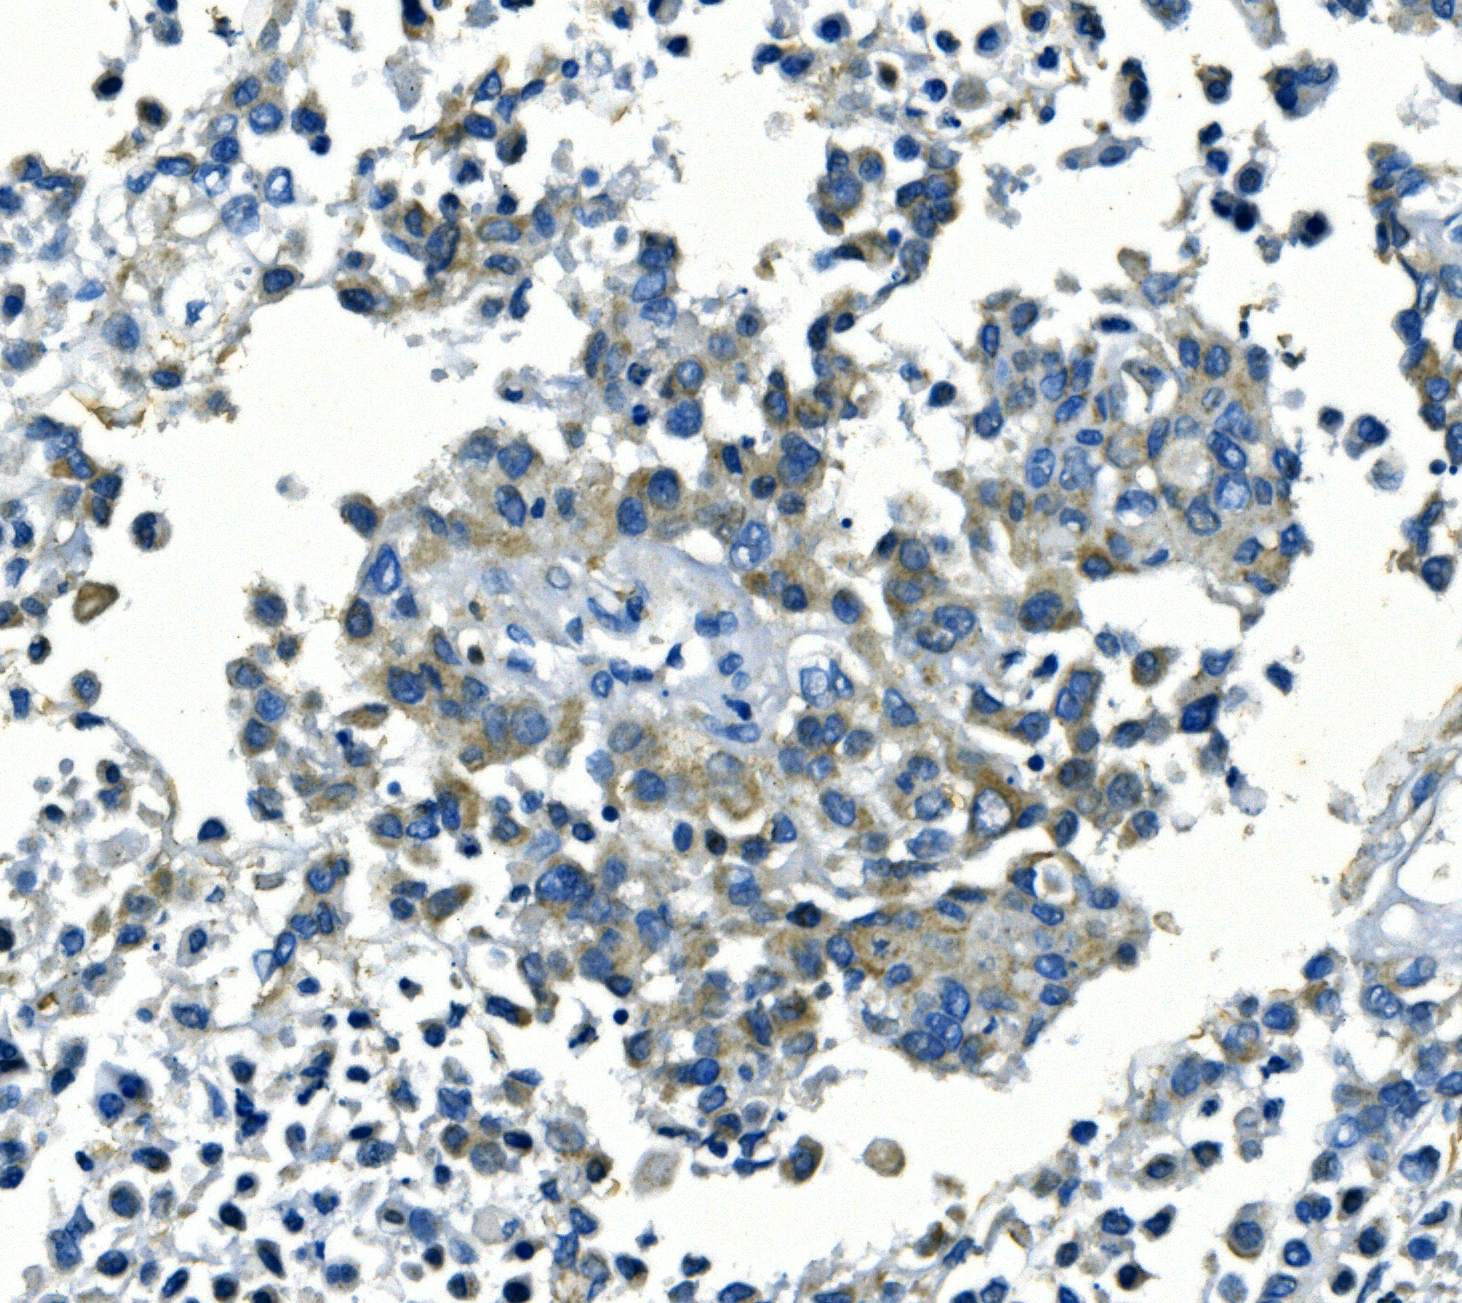

IHC analysis of Kir6.1/KCNJ8 using anti-Kir6.1/KCNJ8 antibody (A04950-1).

Kir6.1/KCNJ8 was detected in a paraffin-embedded section of human pancreatic cancer tissue. Biotinylated goat anti-rabbit IgG was used as secondary antibody. The tissue section was incubated with rabbit anti-Kir6.1/KCNJ8 Antibody (A04950-1) at a dilution of 1:200 and developed using Strepavidin-Biotin-Complex (SABC) (Catalog # SA1022) with DAB (Catalog # AR1027) as the chromogen.